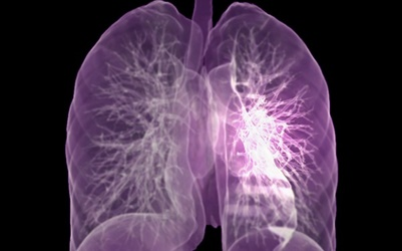

이번 기사에서는 폐암 초기 증상에 대해 자세히 정리해 알려 드리겠습니다 . 폐암은 국내암 사망률 1 위로, 과거에는 흡연이 폐암의 주된 원인 이었지만 , 현재는 비흡연 폐암 환자도 대폭 증가했습니다 . 폐암은 의학 기술로 발달하여 생존율이 높아지고 있습니다 . 폐암의 초기 증상은 무엇인가를 알아보겠습니다.

폐암의 초기 증상